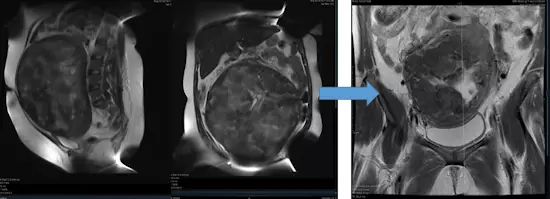

图为 MR 示 29 岁女性多发子宫肌瘤,已无法手术切除肌瘤。而肌瘤栓塞术可以保留子宫和生育能力。患者术后 12 个月后怀孕。